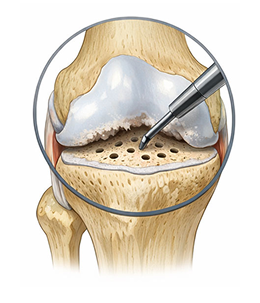

수술적 치료 : 무릎 연골재생술

초기

관절경적 미세천공술(Microfracture)

비교적 작은 연골 결손일 때, 체내 재생을 유도하는 단순하고 부담이 적은 수술입니다.

수술 방법 (어떻게 하는가)

1관절경(내시경)으로 병변 부위 관찰 손상된 연골을 정리

2뼈 표면에 작은 구멍 여러 개를 뚫어 미세천공 시행

3골수에서 재생 세포가 나오도록 유도

4세포들이 굳어져 섬유성 연골(질은 조금 떨어짐)이 새로 채워지는 방식